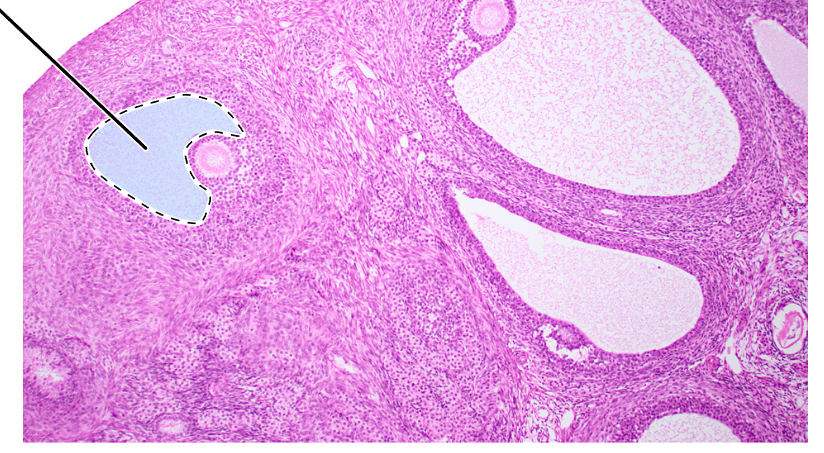

ovary (sagittal section)

cortex

corpus luteum

mature tertiary follicle

antrum

primordial follicles

primary follicle

secondary follicle

tunica albuginea